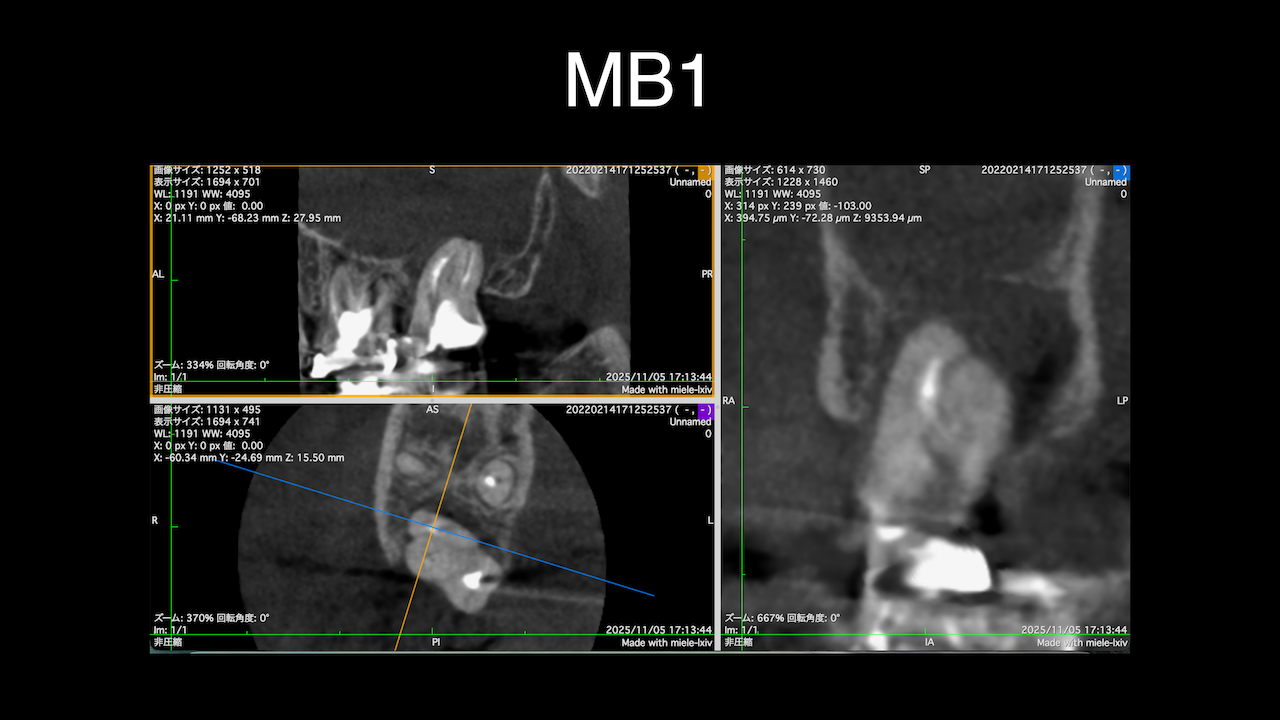

術前にCBCTを撮影したので、MB2がないということを分かった上で根管治療を行っている。

これがCBCTを歯内療法に用いる最大の利点だろう。

#2のMB2はあるのだが、閉鎖していたことと、根尖病変がないのでこのまま終了している。